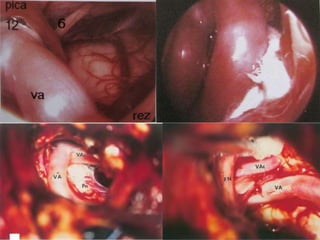

Fig. 26a, b Right side. The root fibers of the hypoglossal

nerve (12) collect in two bundles, which pierce the dura in

two dural pori. The hypoglossal nerve is situated more anteriorly

and medially than the root fibers of the lower cranial

nerves. The arterial relationship is the vertebral artery, with

perforating arteries to the brain stem. The curved vertebral

artery displaces and stretches the hypoglossal nerve fibers.

Through lateral skull base - The

curved vertebral artery displaces

and stretches the hypoglossal

nerve fibers.